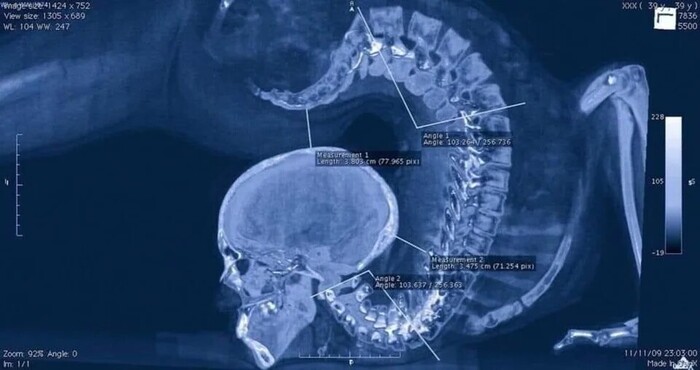

Рентгеновский снимок головы ребёнка

Немного интересных рентгеновских снимков ч.1 Рентген, Историческое фото, Черно-белое фото, Медицина, Наука, Длиннопост